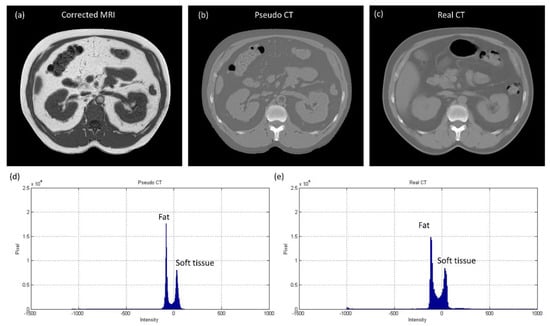

3.2. Abdominal Imaging for Lesion Detection